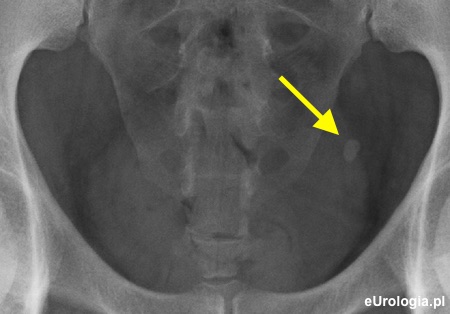

Zdjęcie przeglądowe jamy brzusznej. Widoczny cień wapienny w miednicy małej po stronie lewej o wymiarach 10x7 milimetrów

Zółtą strzałką zaznaczono złóg w lewym moczowodzie o wymiarach 8,7x4,7 milimetra.